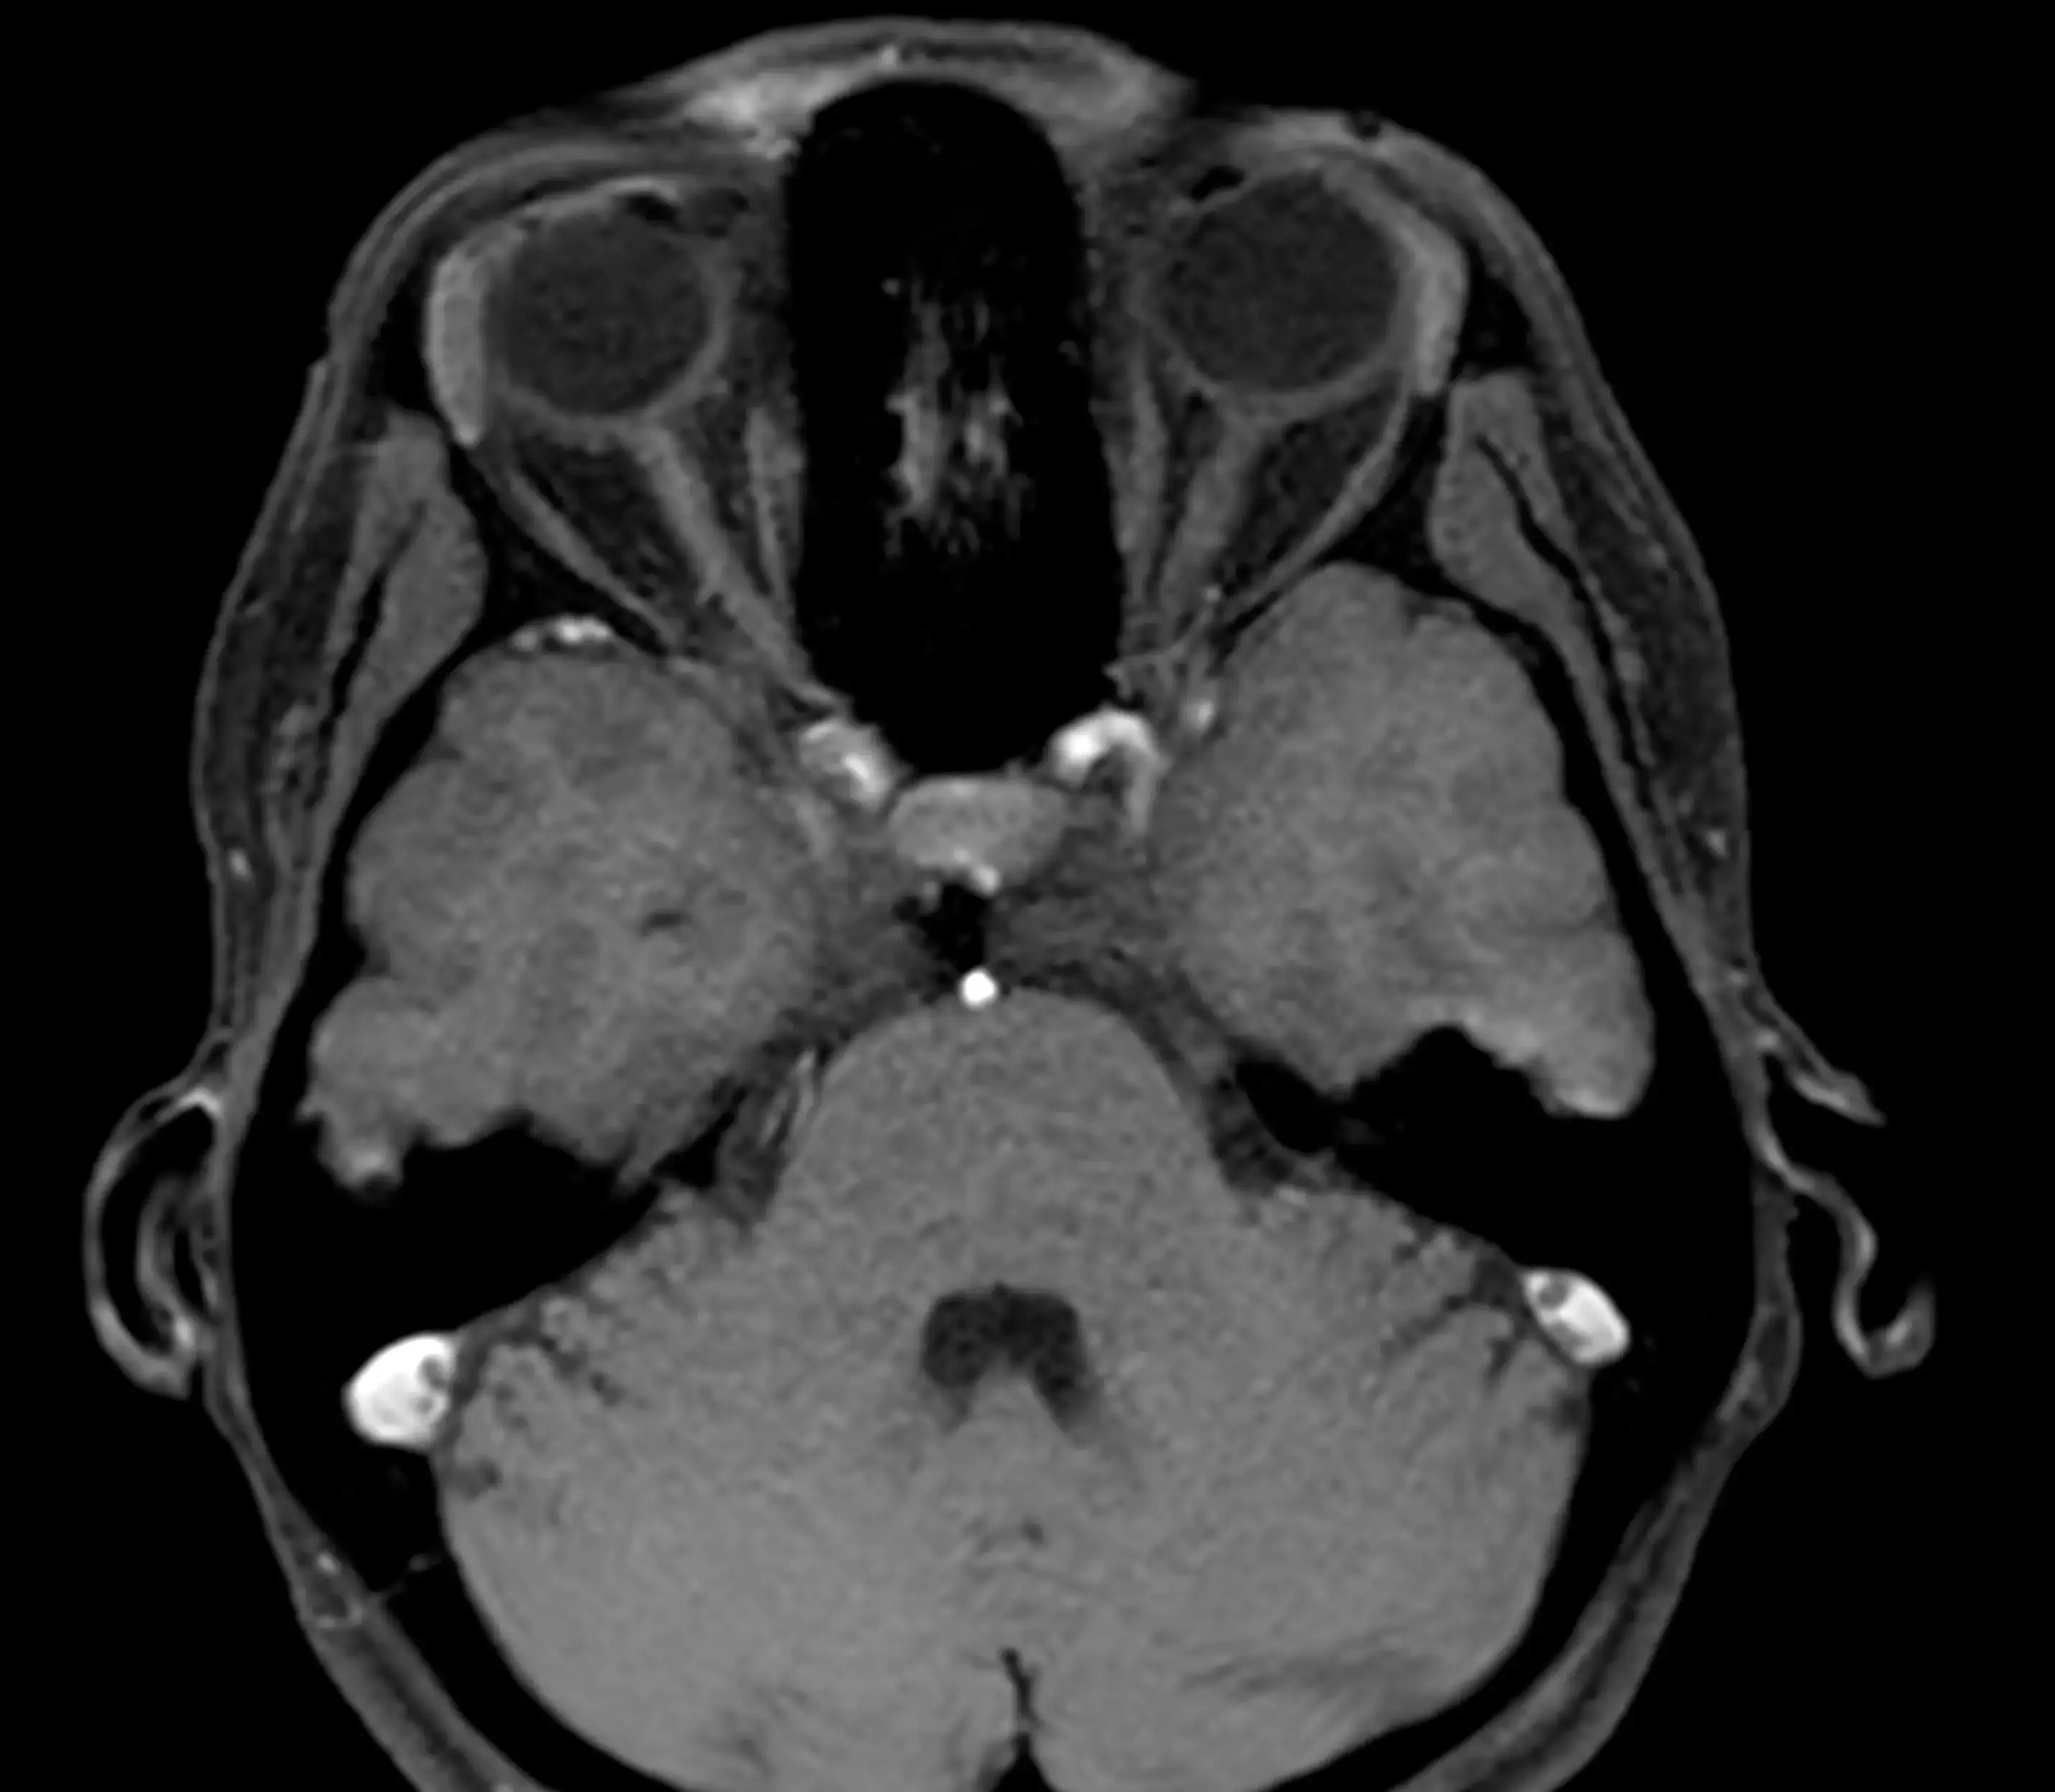

МРТ внутрішнього вуха — це сучасний метод обстеження, який дозволяє детально дослідити структури внутрішнього вуха, слуховий нерв та навколишні тканини.

Магнітно-резонансна томографія допомагає виявити причини порушення слуху, запаморочення та інших неврологічних симптомів без використання рентгенівського випромінювання.

МРТ дозволяє виявити:

- невриному слухового нерва

- пухлини внутрішнього слухового каналу

- запальні процеси

- патології лабіринту

- судинні порушення

- аномалії розвитку внутрішнього вуха

- наслідки травм